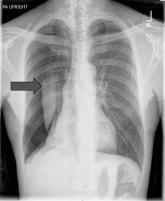

ArticlePneumothorax in a Patient With COPDAuthor:Albert Lu, MD, MSPublish date: April 8, 2010Read More